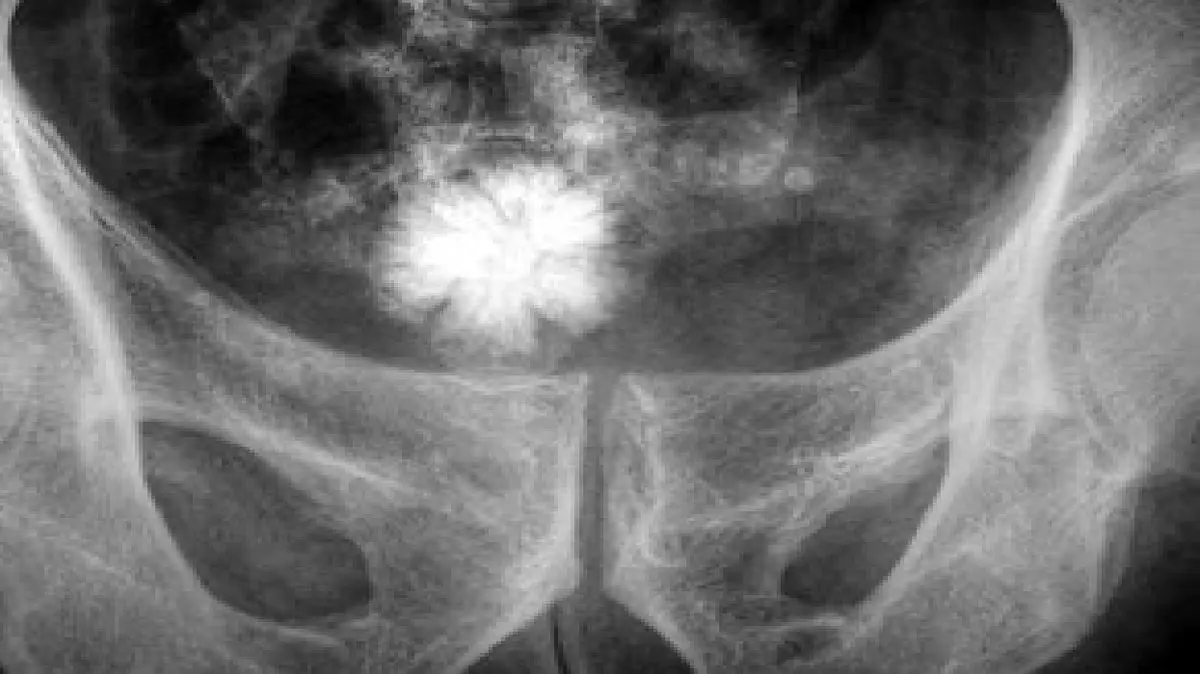

به گزارش رکنا،شاید کمی برای شما عجیب باشد، اما ممکن است درون مثانه تان سنگ ایجاد شود! آیا از علت سنگ مثانه مطلع هستید! این سنگ ها توده های سختی هستند که از مواد معدنی موجود در ادرار به وجود می آیند و بیشتر در مردان بالای ۵۰ سال شایع هستند.

به طور شایع و فراوان وقتی مثانه قادر نباشد ادرار را تخلیه کتد، سنگ مثانه تشکیل می شود. بعضی عفونت ها باعث تشکیل سنگ مثانه می شوند. در بعضی بیماری ها که مثانه را در تخلیه ادرار دچار مشکل می کنند و در نتیجه مثانه ادرار را کامل تخلیه نمی کند، سنگ مثانه تشکیل می شود. اجسام خارجی در مثانه باعث تشکیل سنگ مثانه می شود. برای مثال وقتی سوند فولی خارج می شود ممکن است قسمتی از بالون سوند در مثانه باقی بماند و در آینده هسته اولیه تشکیل سنگ مثانه می شود.

شایع ترین علل تشکیل سنگ مثانه

بزرگی پروستات

به علت انسداد مجرا، مثانه قادر به تخلیه کامل ادرار نخواهد بود و ادرار زیاد در مثانه می ماند و باعث تشکیل سنگ می شود.